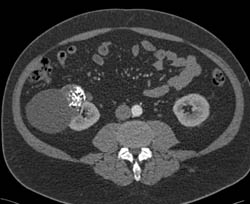

Renal Cell Carcinoma With Renal Vein Extension- See Full Sequence